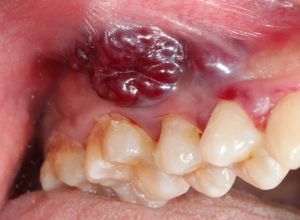

- Atteinte cutanée: le sarcome de Kaposi conduit à l’apparition de taches ou de plaques sur le corps. Le plus souvent, ces macules sont de couleur rouge ou bleu violacé, et peuvent ressembler à des hématomes. Ces taches font du sarcome de Kaposi une maladie affichante et peuvent dans certains cas prendre du relief pour devenir de véritatables nodules cutanés ;

- Atteinte muqueuse: les taches et les lésions peuvent concerner plusieurs muqueuses notamment buccale, oculaire et génitale ;